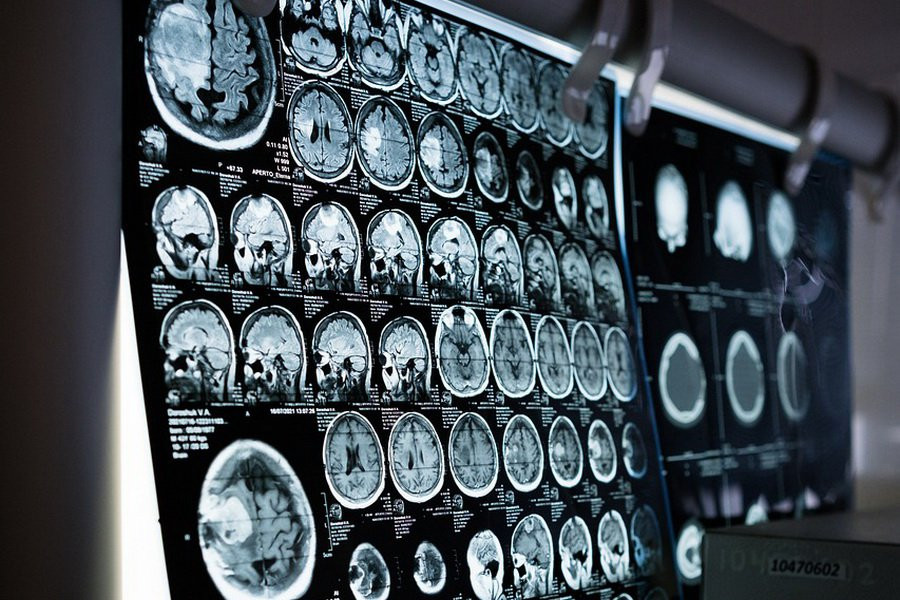

Фото из открытых источников